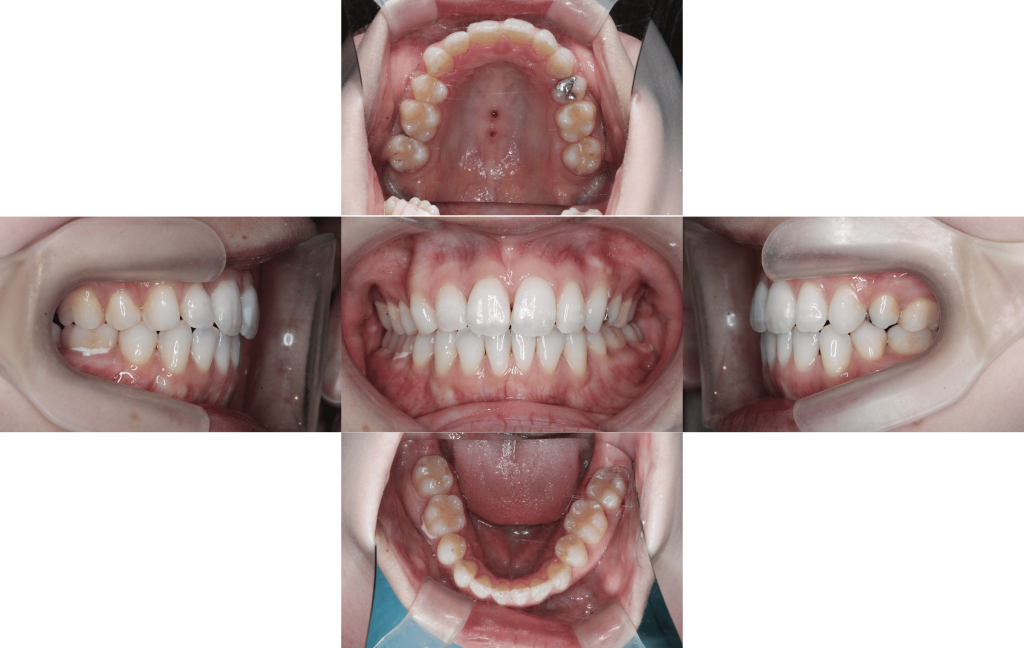

Before

After